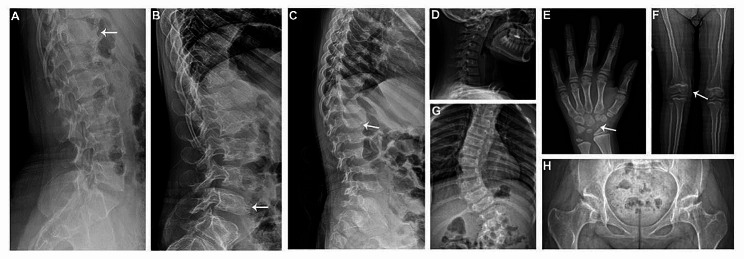

Modification of the vertebral bodies, including platyspondyly, irregularity in the vertebral bodies with “tongue-shaped” deformity and anterior sharpening/beaking of the vertebral bodies, was present on skeletal radiographs of all patients (Fig. 2A-C). In the cervical spine, seven patients showed cervical kyphosis or straight cervical curve (Fig. 2D). In the hands, dysplastic carpal bones were observed in three patients and delayed bone age was noted in two patients (Fig. 2E). Genu valgum was noted in three patients (Fig. 2F). The radiographs of the spine demonstrated scoliosis in six patients (Fig. 2G). All patients showed acetabular and/or femoral head dysplasia (Fig. 2H).

Fig. 2.

Radiographic features in mild patients with MPS IVA. Lateral lumbar spine radiographs showed irregular vertebral bodies with “tongue-shaped” deformity in Pt1 (A), anterior beaking of the vertebral bodies in Pt8 (B) and anterior sharpening of vertebral bodies in Pt9 (C). Radiographs revealed kyphotic cervical curve in Pt6 (D), dysplastic carpal bones (E) and right genu valgum (F) in Pt5, scoliosis in Pt11 (G) and acetabular and femoral head dysplasia in Pt12 (H)